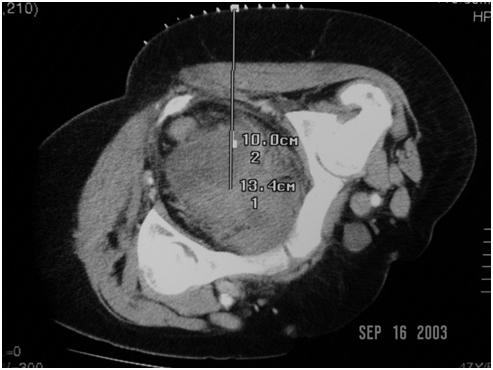

The top-row images belong to a middle-aged woman with skin metastasis from small cell lung cancer who developed a deep pelvic abscess. The first image shows planning of transgluteal drainage of the collection, while the second image captures the final position of a 12F pigtail catheter deployed into it.